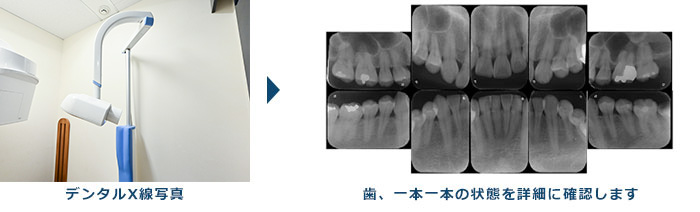

3.エックス線検査

歯周病が進行すると、歯を支えている歯槽骨が溶けてきますので、歯肉の下にある歯槽骨の高さを調べることも必要になります。歯槽骨の状態を調べるのに最も効果的な検査がエックス線検査です。エックス線検査は、歯槽骨の溶けてなくなった範囲や程度をかなり正確に知ることのできる検査になります。

当院では「SIRONA社製 ORTHOPHOS XG」というデジタルエックス線撮影機を使用しており、皆さんが気にされている撮影時の被爆量が最小限で、かつ高精細な画像が得られるように配慮しております。